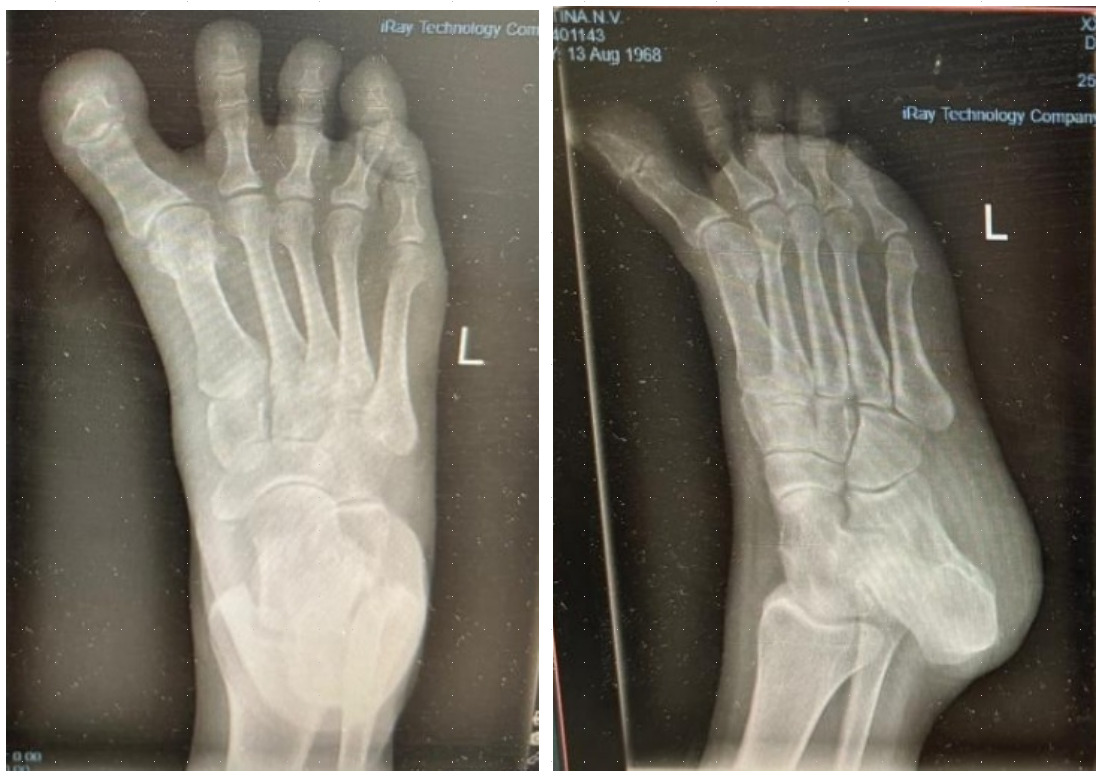

Radiographic evaluation demonstrated effective correction of the hallux alignment. The mean hallux valgus angle (HVA), which was negative in all cases preoperatively (mean –16.5° ± 4.2), improved significantly to a postoperative mean of 5.7° ± 3.2 (p = .0156), with all patients achieving alignment within the physiologic range. Representative radiographs are presented in Figures 1 and 2.

The intermetatarsal angle (IMA) remained stable, changing minimally from a preoperative mean of 3.9° ± 1.6 to 3.7° ± 1.4 postoperatively (p = .6547), suggesting that the procedure achieved targeted realignment of the great toe without affecting the overall first-ray geometry.